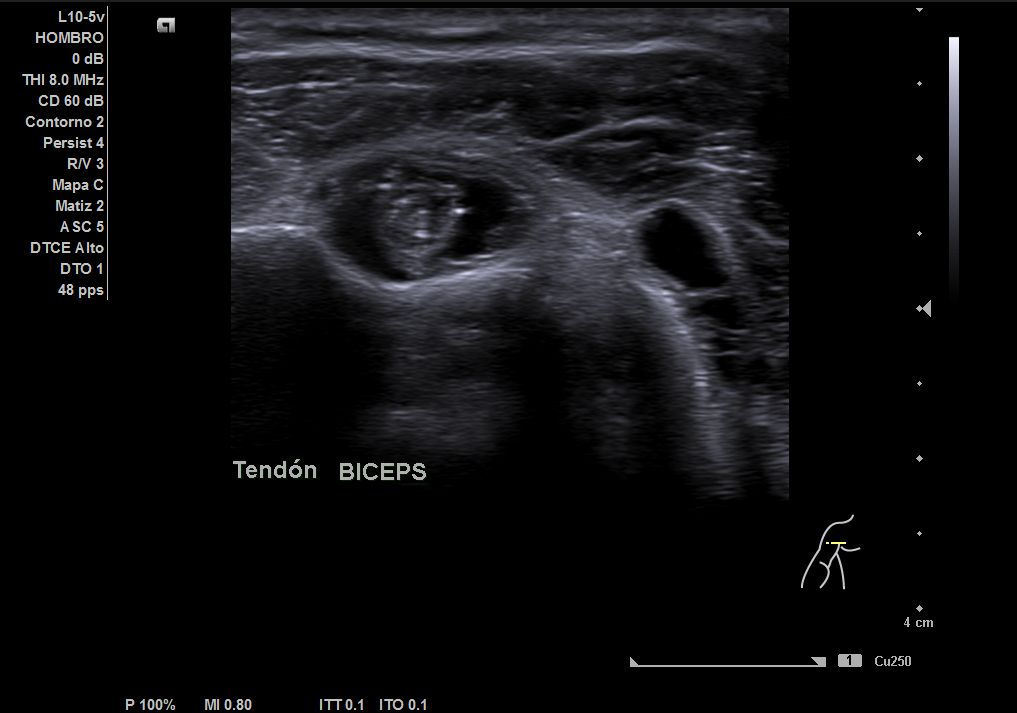

Descripción de los hallazgos ecográficos y las imágenes más relevantes para la resolución del caso

En la ecografía realizada observamos una rotura completa del tendón supraespino, rotura parcial del subescapular y severo derrame peritendón del bíceps junto con derrame articular glenohumeral.

Se optimizó el tratamiento analgésico pautado y se ofreció a la paciente la infiltración ecoguiada, que rechazó en ese momento. Además se amplió el estudio a una resonancia magnética para confirmar los hallazgos que encontramos con la ecografía clínica realizada en el Centro de Salud.

Al observar dichos hallazgos decidimos pedir una resonancia magnética que confirmó los hallazgos. Posteriormente derivamos a traumatología que citó a la paciente e indicó que sería candidata a cirugía de colocación de prótesis invertida que ella rechazó. Posteriormente a la semana, volvió a nuestra consulta indicando que el dolor había aumentado y se le realizó la infiltración.